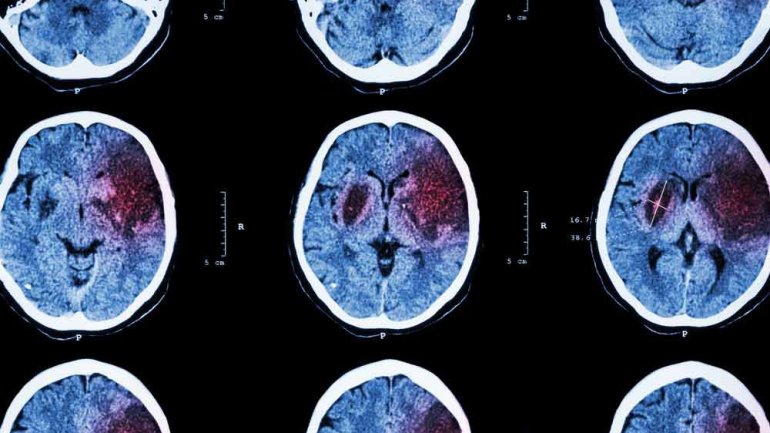

Ερευνητές στο Πανεπιστήμιο του Tampere έδειξαν για πρώτη φορά ότι η εγκεφαλική εμβολή ασθενών με εγκεφαλικό επεισόδιο περιέχει DNA από παθογόνα του στόματος.

Η θρόμβωση της εγκεφαλικής αρτηρίας προκαλεί το 87% των εγκεφαλικών επεισοδίων. Οι περισσότεροι θρόμβοι προέρχονται από την καρωτιδική αρτηρία από όπου ταξιδεύουν για να μπλοκάρουν την εγκεφαλική κυκλοφορία.

Τα αποτελέσματα έδειξαν ότι μια μεγάλη ποσότητα DNA από streptococcus viridans – φυσιολογικά βακτήρια στο στόμα – βρέθηκε σε εγκεφαλικούς θρόμβους, σε σύγκριση με τα φυσιολογικά δείγματα αίματος από τους ίδιους ασθενείς.